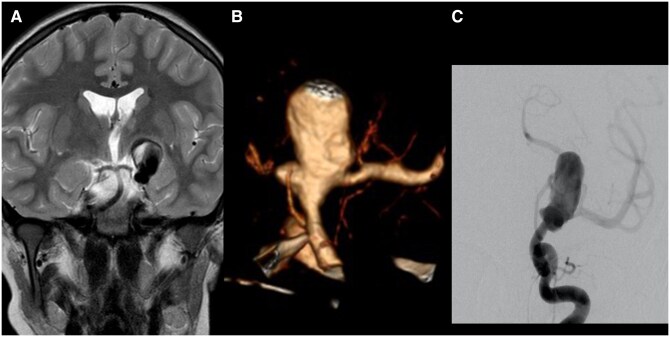

A 28-mm diameter and partially thrombosed intracranial aneurysm was found in a 10-year-old boy on an MRI for non-specific headaches. The large neck incorporated the left internal carotid artery (ICA) termination and proximal middle cerebral artery. Treatment was planned to prevent further growth and rupture. Because of the difficult anatomy, a braided stent was first placed across the aneurysm neck as a scaffold to allow for the placement of a flow-diverting stent after its endothelialisation. However, severe stent-induced endothelial hyperplasia was encountered when the flow diverter was inserted. This resulted in a transient ICA occlusion during the procedure before flow was restored by angioplasty. As a result, the patient suffered a mild transient dysphasia but permanent loss of vision in the left eye. All antiplatelet medications were stopped 1 year after the procedure without problem. The aneurysm has remained fully occluded in the 7 years since.